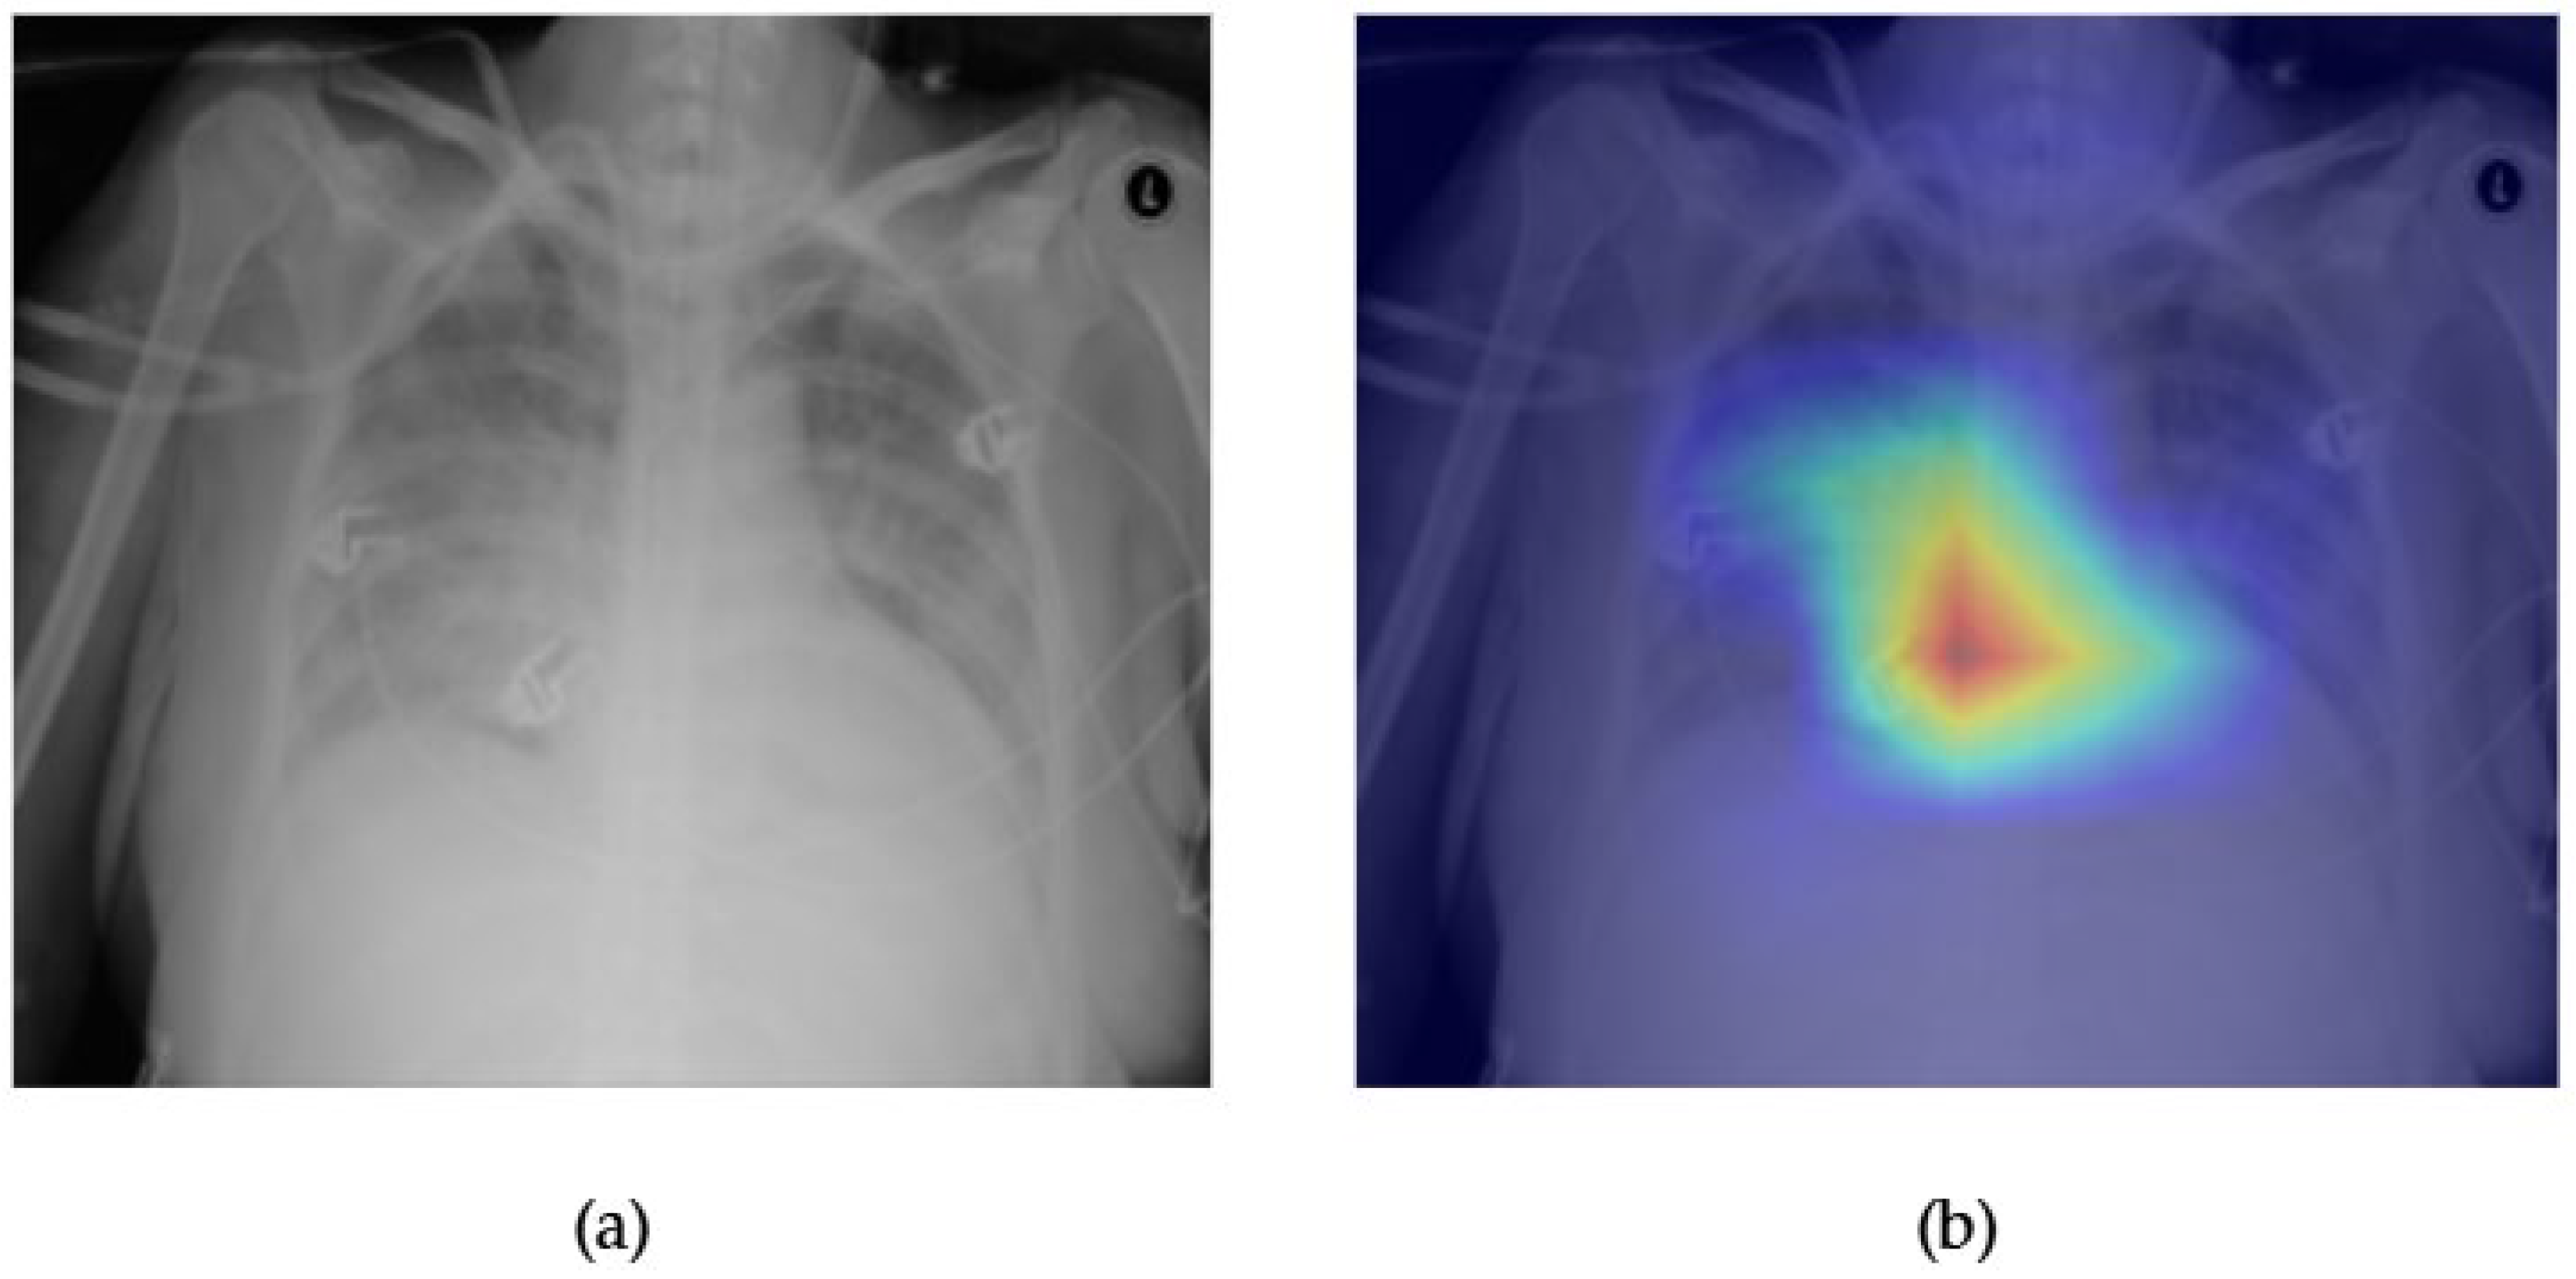

- Although our Grad-CAM-based explainability provides useful localization cues, it is inherently limited by its post hoc nature and reliance on gradient flow from the final convolutional layers. Future research could incorporate advanced interpretability techniques such as Layer-wise Relevance Propagation (LRP), Integrated Gradients, or attention rollouts in Transformers, which may offer a more complete understanding of model reasoning.